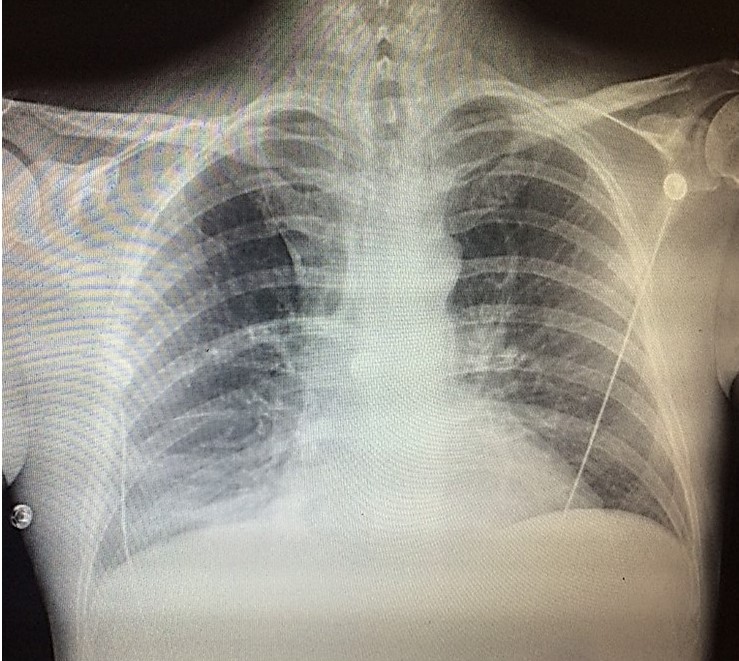

Because of the COVID19 pandemic, you are practicing telemedicine. You are shown the

chest x-rays and an EKG of a 65-year-old man who is complaining of shortness of breath.

DIAGNOSIS: S1Q3T3 pattern in a patient with pulmonary embolism (note the right lower

lobe infiltrate in the PA film and the wedge-shaped infiltrate in the lateral film).